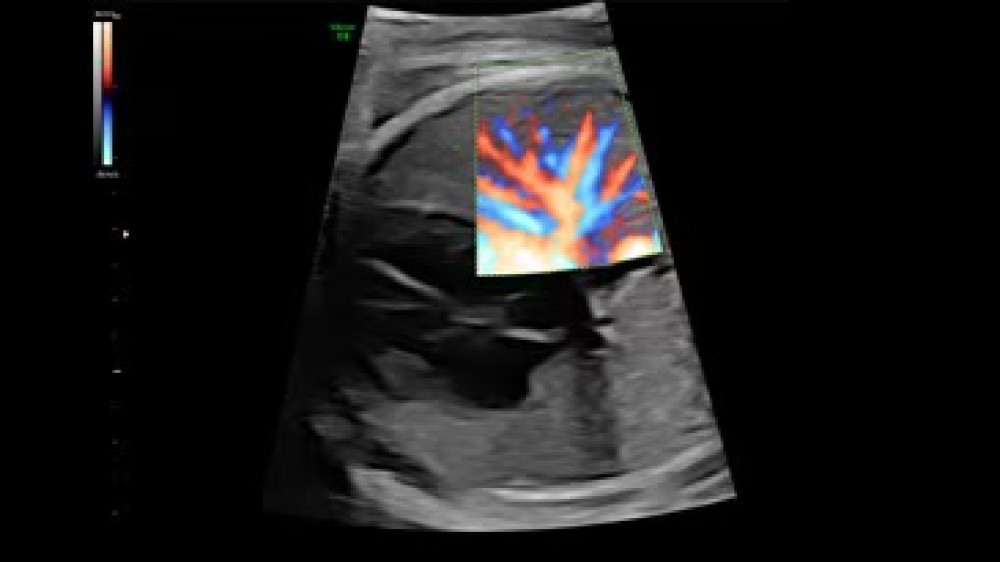

Voluson E6 GE Healthcare-in orta-yüksək səviyyəli ultrasəs cihazıdır və əsasən qadın sağlamlığı, obstetrik və ginekoloji müayinələr üçün nəzərdə tutulub. Sistem Radiance System Architecture üzərində qurulub və bu, yüksək keyfiyyətli 2D və 3D/4D görüntüləmə, həmçinin Color Doppler funksiyasını təmin edir.

Voluson E6-in avtomatlaşdırılmış funksiyalarıergonomik dizaynı operatora iş axınını optimallaşdırmaq, müayinələri daha sürətli və səmərəli icra etmək imkanı verir. Sistem fetal inkişafın, plasentanın, ürək fəaliyyətinin və qadın reproduktiv sisteminin dəqiq qiymətləndirilməsi üçün nəzərdə tutulmuşdur, eyni zamanda gündəlik klinik iş yükünü asanlaşdırır.